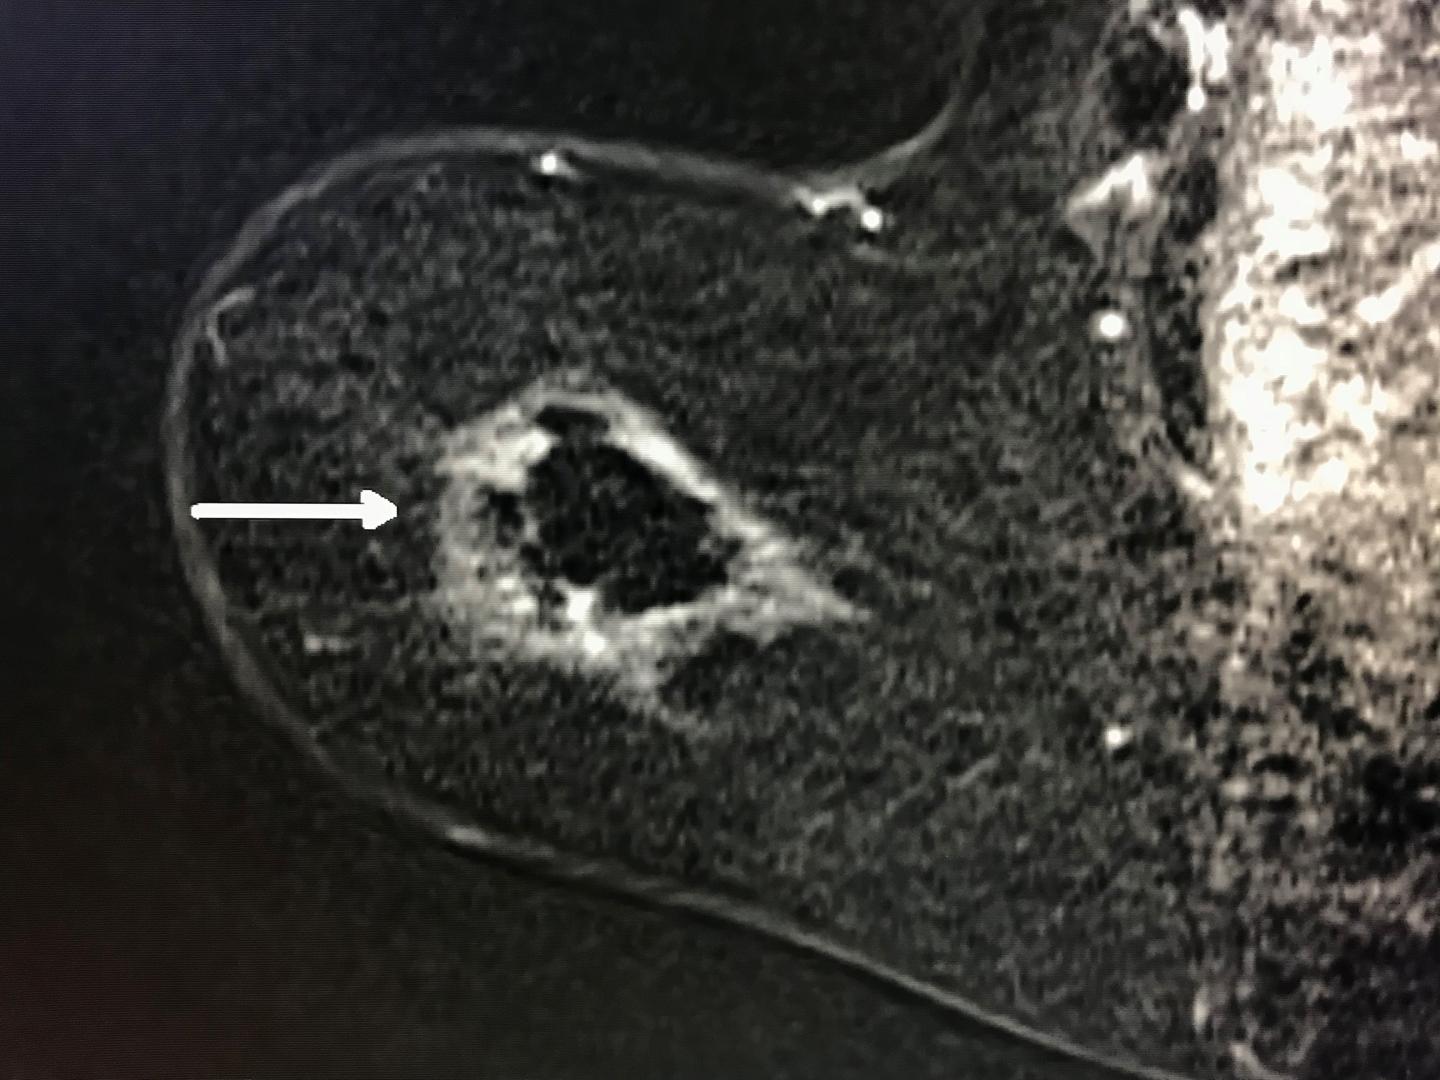

Cryoablation represents a potential new weapon in the arsenal against breast cancer. The procedure begins with the introduction of a probe into the tumor through a pea-sized incision in the skin while the patient is under local anesthesia. The probe is guided by high-definition ultrasound in conjunction with mammography images. Once the probe is in place, liquid nitrogen is introduced into it. During the initial, eight-minute freeze cycle, an ice ball forms around the tumor, killing the cancer. After a thaw cycle, another eight-minute freeze cycle is used to ensure complete destruction of the cancer cells. The procedure takes less than an hour, and patients are able to return to their normal activities shortly thereafter.